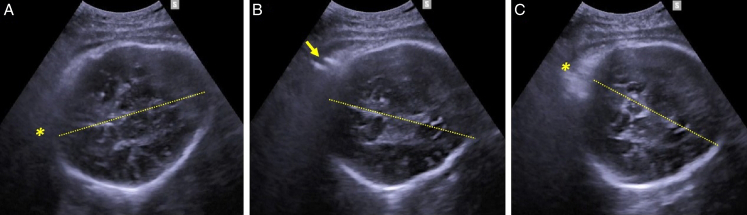

Intrapartum ultrasound (US) is more reliable than clinical assessment in determining parameters of crucial importance to optimize the management of labor including the position and station of the presenting part. Evidence from the literature supports the role of intrapartum US in predicting the outcome of labor in women diagnosed with slow progress during the first and second stage of labor, and randomized data have demonstrated that transabdominal US is far more accurate than digital examination in assessing fetal position before performing an instrumental delivery. Intrapartum US has also been shown to outperform the clinical skills in predicting the outcome and improving the technique of instrumental vaginal delivery. On this basis, some guidelines recommend intrapartum US to ascertain occiput position before performing an instrumental delivery. Manual rotation of occiput posterior position (MROP) and assisted breech delivery of the second twin are other obstetric interventions that can be performed during the second stage of labor with the support of intrapartum US. In this review article we summarize the existing evidence on the role of intrapartum US in assisting different types of obstetric intervention with the aim to improve their safety.